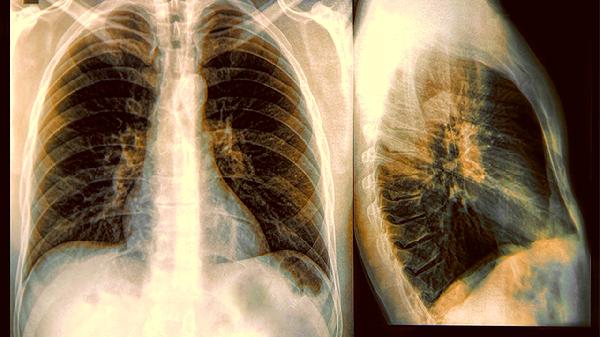

当这些信号组合出现时,别急着往感冒药箱里翻找解决方案。及时进行血常规和胸部影像学检查,能清晰揭示问题的真正所在。肺部就像娇嫩的蜂巢,早期干预可以避免肺泡结构被永久破坏。记住,咳嗽超过10天不缓解、发热反复发作、痰中带血丝,这三条出现任意一条都该敲响警.钟。保持呼吸道湿润,避免二手烟刺激,接种相关疫苗,都是守护这道呼吸长.城的重要措施。